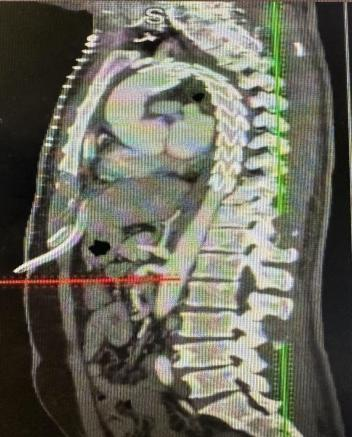

术前3D重建

术后胸主动脉CTA重建